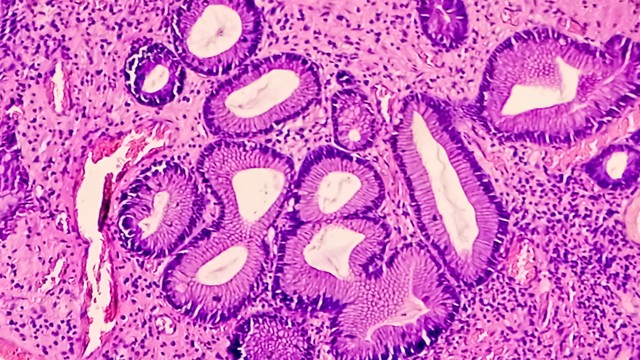

Polyp dạ dày là những khối u nhỏ phát triển từ lớp niêm mạc dạ dày, thường được phát hiện tình cờ khi nội soi tiêu hóa. Nhiều người lo lắng polyp dạ dày có phải là ung thư không? Liệu có nguy hiểm gì không?